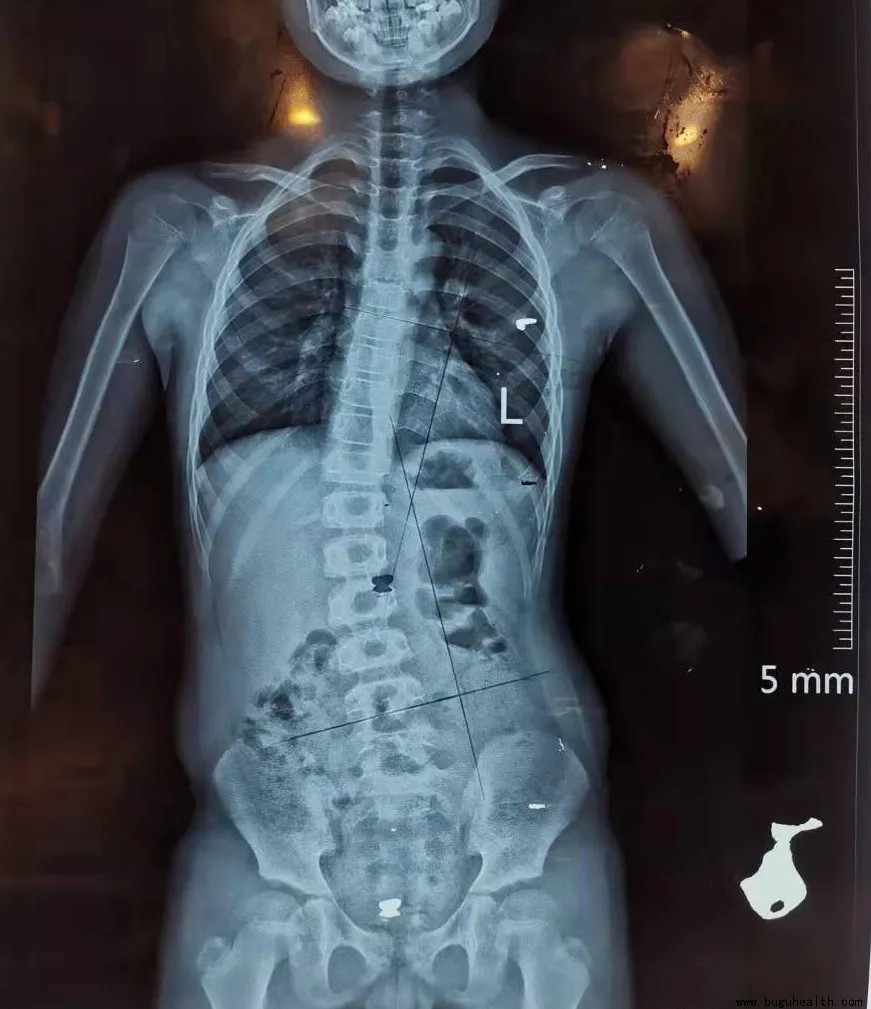

正常人的脊柱从正面或者背面看是直的,那么脊柱侧弯的患者如果检查脊柱全长X光片就会发现,自己的脊柱有了弯曲。为了便于观察侧弯畸形的进展及评估,著名的美国矫形外科医生John Robert Cobb教授(1903-1967)于1948年发明了简便实用的Cobb角测量法则,目前仍然是脊柱侧弯矫形医生最常用的方法:

1.此弯的上端及下端分别找到倾斜度最大的椎体,为上下端椎;

2.于上端椎的上缘,下端椎的下缘分别画平行线;

3.做两条平行线的垂线。

4.测量垂线的夹角。

简单来说就是4个步骤:上下端椎的选择,画平行线,做平行线的垂线以及角度测量;

测量结果:Cobb角<10°为阴性,10°≥Cobb角<20°为阳性,Cobb角>20°为明显阳性;即Cobb角>10°为脊柱侧弯。

注:画平行线时以椎体终板连线为准,如果X线片显示不清晰,此时常用椎弓根连线代替椎板连线;对于较大的侧弯,上述两平行线的交角亦等同于Cobb角。